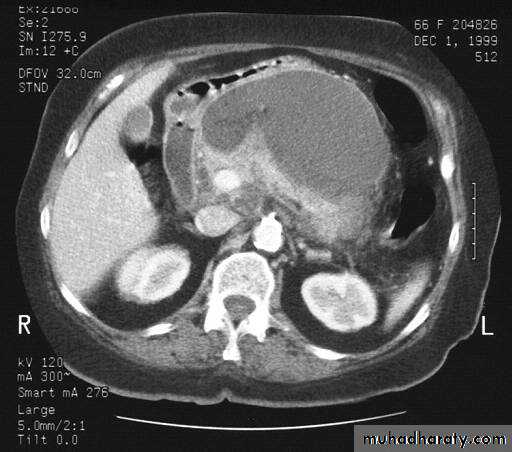

Secondary metastasis in the liver

Multiple rounded hypo density areas of different density , shape & different size .

Pattern of enhancement is either uniform , target or bulls eye pattern .

Hepato megaly .